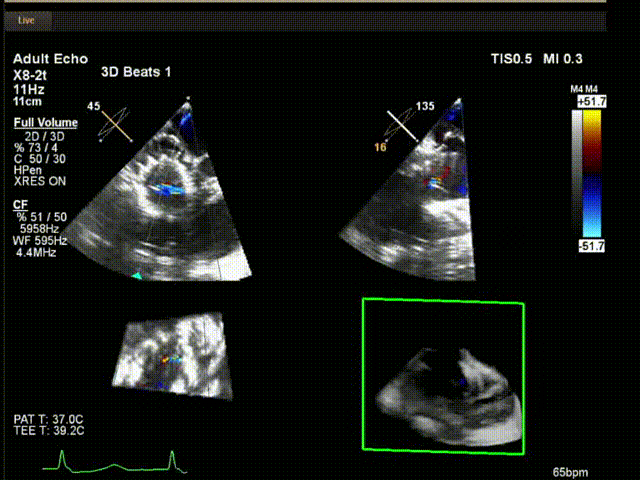

術(shù)中超聲

陸方林教授通過遠程線上帶教的方式,與林逸賢教授團隊共同完成了此次LuX-Valve Plus人工瓣膜的首例植入。術(shù)后食道超聲提示三尖瓣反流完全消失,無瓣周漏,且LuX-Valve Plus人工瓣膜的兩個夾持鍵成功抓取瓣葉,錨定牢固,人工瓣膜穩(wěn)定性良好。

手術(shù)在全麻狀態(tài)下開展,此次手術(shù)采用經(jīng)頸靜脈入路的方式。在TEE及DSA雙重引導(dǎo)下,術(shù)者調(diào)整輸送器頭端角度使得其與三尖瓣瓣環(huán)平面垂直。在輸送器進入右心室后釋放室間隔錨定裝置,而后釋放瓣葉夾持件(2個耳片結(jié)構(gòu))成垂直狀態(tài)。在TEE及DSA確定夾持件固定至三尖瓣葉根部且位于右室側(cè)后釋放人工瓣心房側(cè)盤片。隨后調(diào)整瓣膜同軸性以及室間隔錨定件位置(貼合室間隔),進而釋放室間隔錨定裝置,并再次確認瓣膜位置、穩(wěn)定性及同軸性,解離人工瓣膜與輸送器間連接,并撤出輸送器,完成了LuX-Valve Plus人工三尖瓣瓣膜的植入。